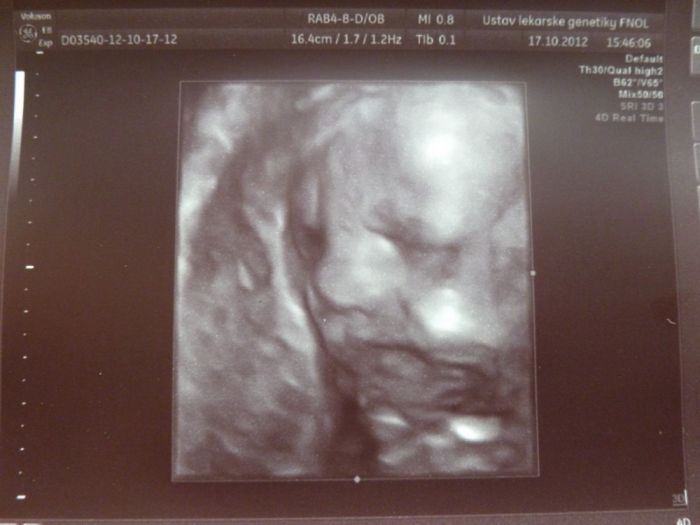

Tak máme za sebou ten 3D ultrazvuk, bála jsem se že nebudeme nic vidět, ale malá byla vidět krásně, je to nejkrásnější miminko na světě už teď

- jako samozdřejmě pro každou mamku to její

. Paní doktorka nám ji teda potřetí potvrdila, tak snad se z ní už ten kluk nevyklube

, máme 13.minut video a 4 fotky, jsem fakt spokojená, je tak sladkááá

. No fotečky vám sem dám dvě, na jedné se pěkně mračí, asi ji to už nebavilo

.